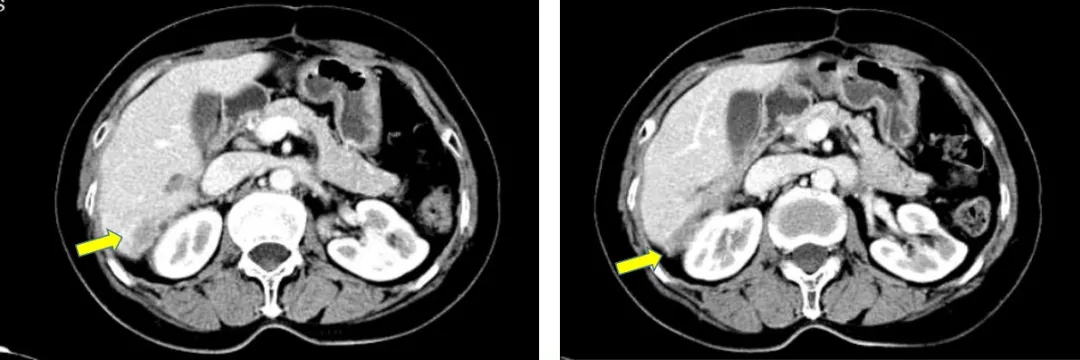

2013.5.6在我院(中国科学院大学附属肿瘤医院)检测CA125水平为298.8U/ml。CT:胸部(-),肝肾隐窝异常信号,脾脏前内方囊性占位灶,考虑转移灶;肠系膜上动脉水平、腹主动脉偏左侧结节灶;盆腔(-)。

2013.5.10 PET-CT:肝肾隐窝、脾肾间隙、脾门旁、腹膜后可见斑片状、囊实性及结节状影,实质部分FDG代谢增高,考虑转移。

2013.5.10 PET-CT检查结果